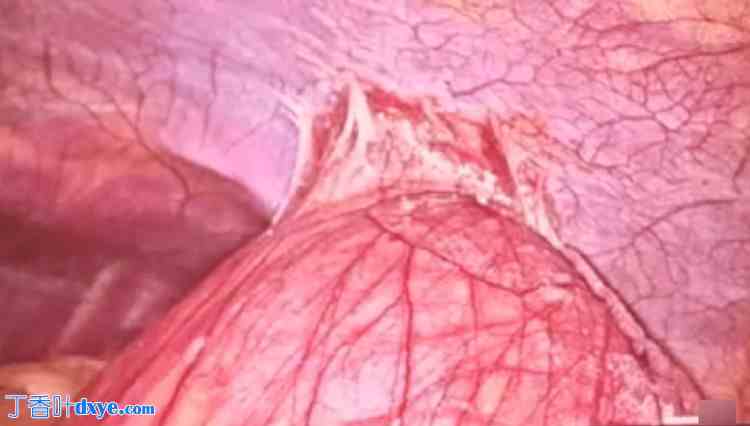

一名30岁男性患者因剧烈、进行性、钝痛性、全身性腹痛两天来门诊就诊。患者无腹胀、呕吐或顽固性便秘。体格检查:患者脉搏116次/分,血压130/86毫米汞柱。腹部检查发现脐区、左季肋部和左腰部有压痛,无其他明显异常,例如腹胀、肌紧张或肌强直。直肠指检未见异常。腹部X光片显示左腰部有少量扩张的肠管。膈肌两侧穹窿下无游离气体,提示有空腔脏器穿孔。增强CT扫描(CECT)显示左侧PDH(图1)。

图 1. 该病例的增强CT图像。

A、B:红色箭头指示囊内扩张的空肠袢突出至左结肠系膜。空肠袢显示血管分布正常。